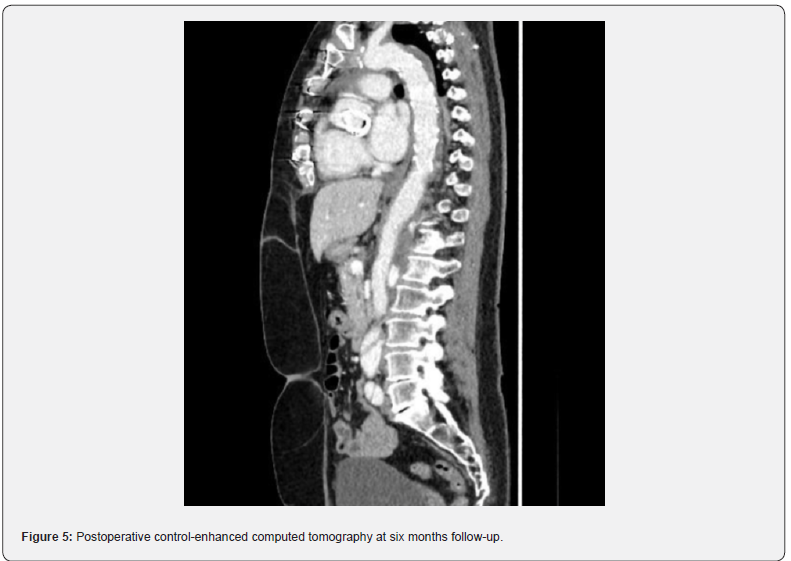

A 59-year-old female patient suffering from recurrent chest pain after acute Stanford Type A aortic dissection (TAAD) presented at our outpatient clinic. Four months prior to this consultation, the patient underwent emergency surgery with aortic root remodeling and replacement of the ascending aorta in deep-hypothermic arrest at another centre. The postoperative period was complicated by pulmonary insufficiency with prolonged ventilation. At the present visit in our department, a control contrast-enhanced computed tomography was performed showing a rest dissection starting at the distal ascending aorta was seen (Figure 1). Additionally a moderate aortic valve regurgitation was seen at transesophageal echocardiography (Figure 2). The patient was urgent taken to the operating theatre for complete open repair. Cardiopulmonary bypass was initiated by re-cannulation of the right axillary artery and the right femoral vein. Hypothermic circulatory arrest at 17.7°C was instituted for implantation of a frozen elephant trunk (E-vita OPEN PLUS Hybrid Stentgraft System 24mm with a stentgraft length of 130mm; Jotec GmbH, Hechingen, Germany), arch replacement and replacement of the aortic valve using a rapid-deployment valve system (23mm) after removing the native aortic valve leaflets. Antegrade brain perfusion was performed for 42 minutes and cross-clamp time was 93 minutes. The postoperative course was uneventful and respirator weaning was achieved within 5 hours. On postoperative day 2, the patient was transferred to the general ward. The patient was discharged home on postoperative day 14 showing excellent aortic valve function, without regurgitation and optimal aortic repair (Figure 3,4). On 6 months follow-up these data could be confirmed (Figure 5).